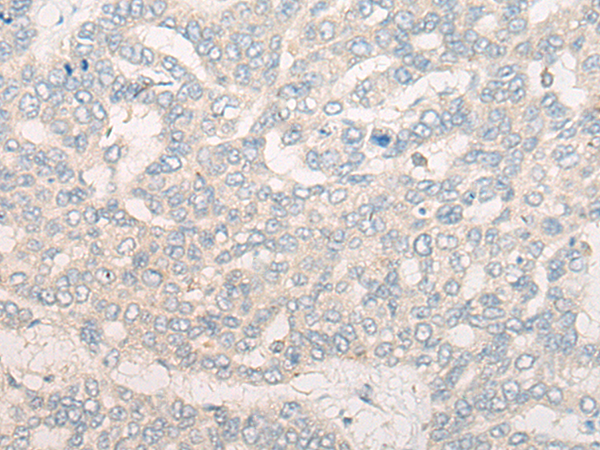

IHC positive control: |

Human liver cancer and Human gastric cancer |

IHC Recommend dilution: |

20-100 |